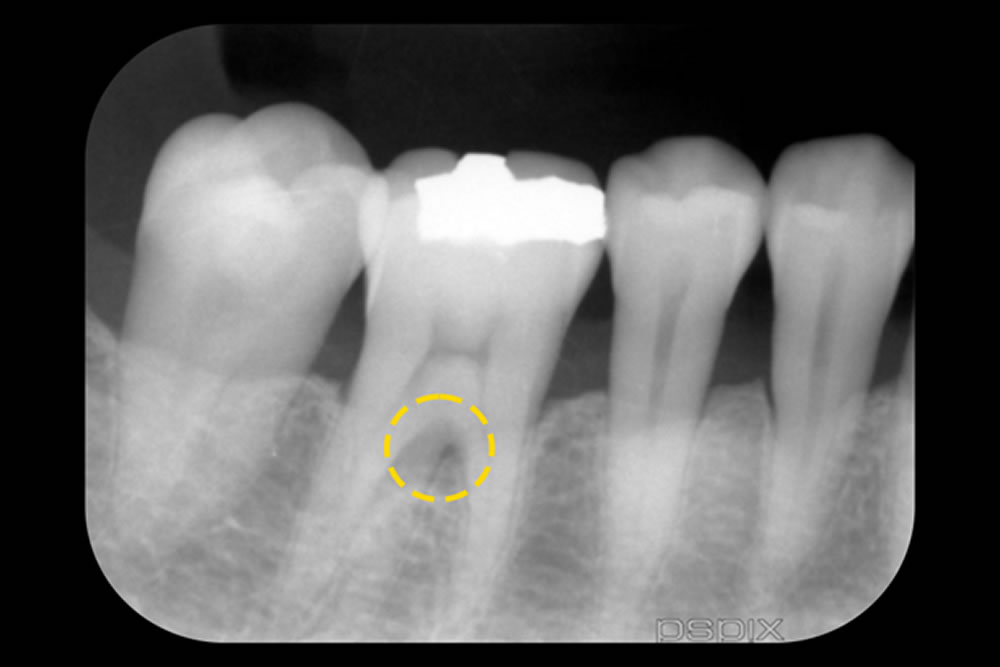

初診時(上写真)、右下6番目の歯は今にも抜け落ちそうな状態でしたが、重度歯周病治療【MINST】によって、症状を改善し、術後1年後(下写真)には歯周組織もしっかりと再生しました。

※外科処置なし・再生材料も使用しておりません。